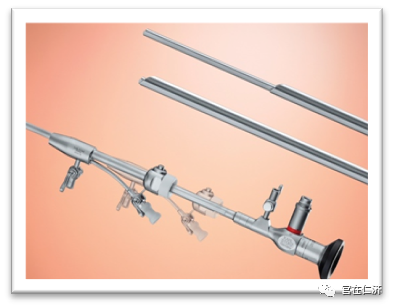

A: 药物治疗对子宫内膜息肉的作用有限。手术治疗是内膜息肉最常用的治疗手段,目前指南推荐宫腔镜手术取代盲目刮宫作为内膜息肉的首选治疗。我们中心采用的IBS刨削装置,手术时间短,息肉切除完整,且没有电损伤,可以较好的保护内膜功能